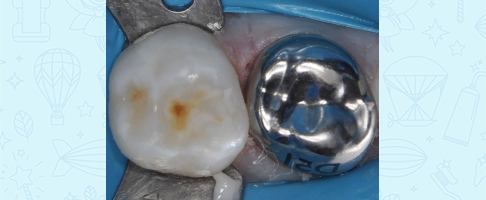

Лечение кариеса, восстановление зуба коронкой

Лечение кариеса молочного зуба, восстановление коронкой и герметизация фиссур с применением закиси азота

Лечение кариеса и пульпита молочных зубов во сне, восстановление коронками

Лечение пульпита молочного зуба, восстановление коронкой

Лечение пульпита молочного зуба, восстановление коронкой

Лечение пульпита молочного зуба, восстановление коронкой